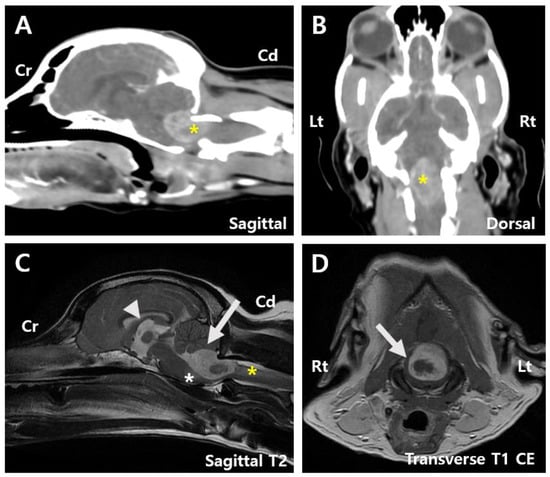

Postoperative CT indicated a lesion with heterogeneous contrast enhancement at the cranial aspect of the foramen magnum, potentially related to the patient’s history of a fourth ventricle tumor resection, suggesting a residual tumor lesion (Figure 3A,B). Postsurgical changes were observed at the level of the internal occipital crest and dorsal subquadrant. Peripheral rim-enhancing and fluid-attenuating lesions were identified in the rectus capitis dorsalis muscle (Figure 3A).

MRI findings showed that the mass within the fourth ventricle and the peripheral region was characterized by T2 hyperintensity, T1 hypointensity, and contrast enhancement. The mass had decreased to approximately 19% of its original size and measured 0.9 cm × 0.7 cm × 1.3 cm (Figure 3C,D). Compression of the cerebellum and medulla oblongata was also reduced. The subarachnoid space thinning that was observed preoperatively was no longer present. Additionally, a well-defined, round to oval-shaped lesion measuring 1.8 cm × 0.8 cm × 1.0 cm was identified within the rectus capitis dorsalis muscle, adjacent to the tuber and pyramid of the cerebellar vermis. The lesion exhibited T2 and FLAIR hyperintensities, T1 hypointensity, and peripheral contrast enhancement (Figure 3C). A reduction in third ventricle dilation was also noted compared to preoperative imaging (Figure 3C).

Figure 3. Post-surgery images. (A) Sagittal CT image of the patient reveals a contrast-enhancing tumor measuring 0.9 cm × 0.7 cm (arrow), along with a peripheral rim-enhancing and fluid-attenuating lesion identified within the rectus capitis dorsalis muscle (asterisk). (B) Dorsal CT image showing a contrast-enhancing tumor measuring 0.9 cm × 1.3 cm (asterisk). (C) Sagittal T2 MRI image showing peripheral T2 hyperintense lesions surrounding the mass (white arrow), a reduction in the previously dilated third ventricle (arrowhead), and a contrast-enhancing round to oval-shaped lesion measuring 1.8 cm × 0.8 cm × 1.0 cm surrounded by the overlying muscles including the rectus capitis dorsalis (asterisk). (D) Transverse T1 MRI image showing hypointense lesions (white arrow). Cd, Caudal; Cr, Cranial; Lt, left; Rt, right.